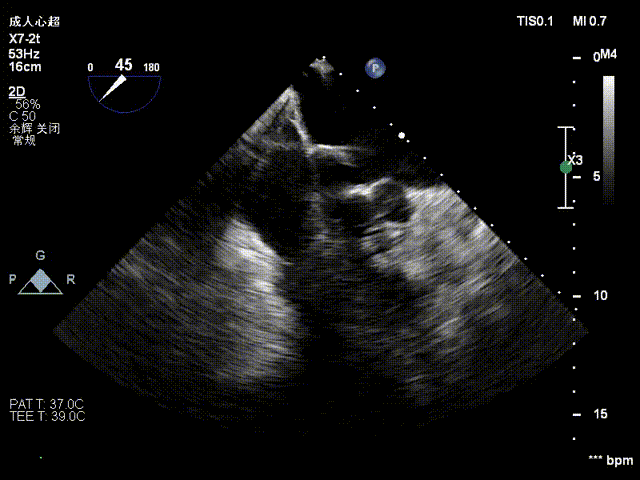

术前影像

手术难点/病例特征

该病例为二尖瓣重度反流,前叶A3区瓣叶脱垂并并腱索断裂,后叶瓣叶合并钙化,捕获瓣叶有一定难度。拟植入一枚NeoNova®C6(宽6mm)夹合器于3区脱垂处解决主要脱垂,然后根据残余反流和瓣口面积条件判断是否需要植入第二枚夹合器。